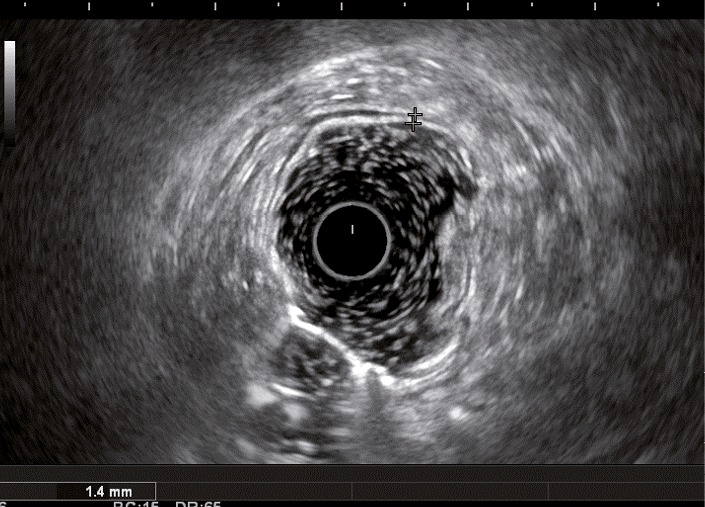

Рис. 2. Эндосонографическая картина стенки толстой кишки в норме